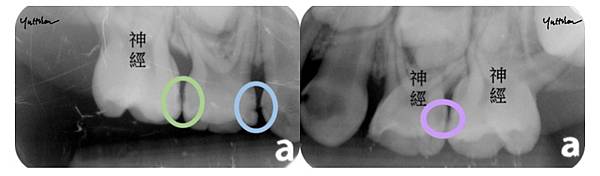

在我們看不到的地方

蛀牙可能已經偷偷侵犯了